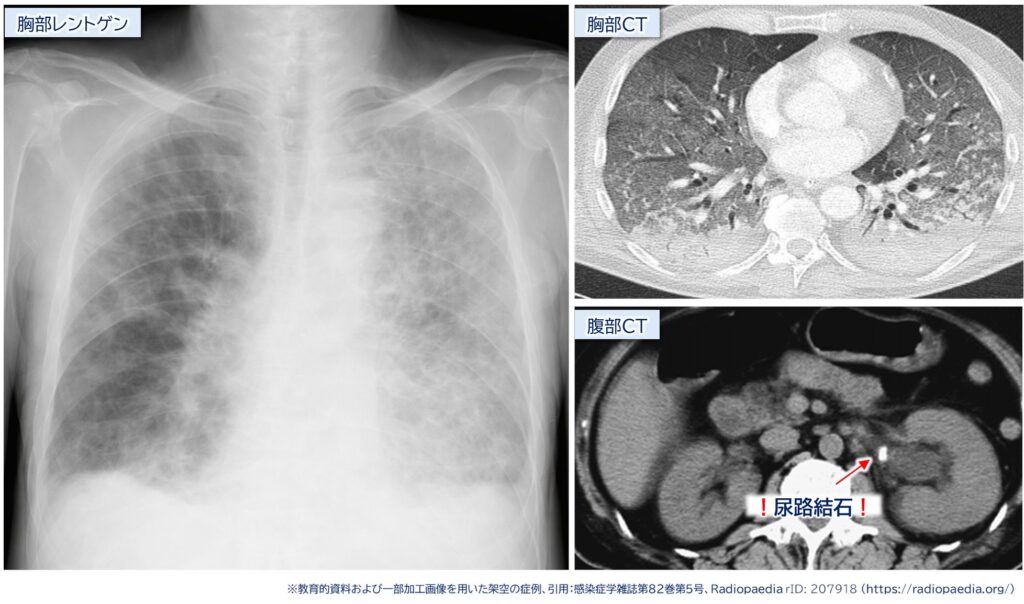

他院から救急搬送、62歳男性。

発熱、呼吸困難、レントゲンで肺水腫?

こ、これは、尿路結石→腎盂腎炎→敗血症→ARDSって流れか~!

——そして胸腹部CT——

指導医「才能の塊やないかい」

・胸部画像で両側性の浸潤影

実際には、画像で直接・間接傷害を区別することは難しく、混在したパターンも示します。しかし、典型的な画像・臨床像も一定数存在するため、その特徴を知っておくことに損はありません。

また、レントゲンでは肺水腫様に見える所見でしたが、胸部 CTでは間接傷害を疑う分布を示しており、さらに肺炎と考えるには咳や痰といった気道症状が乏しい点にも違和感を持ちました。

そこに、患者さん自身から「尿路結石の既往」というヒントを踏まえ、尿路結石嵌頓 → 腎盂腎炎 → 敗血症 → ARDSという病態を連想できた点は、非常におてがらポイントです。

本症例は、若手医療者に対して 「両側性の浸潤影や肺水腫様パターンの画像を見た際に、肺炎か心不全だけでなく、肺外原因によるARDSも鑑別に挙げる重要性」を伝えることを目的としています。

なお、本エピソードは過去の実例をもとに再構成した 架空症例です。掲載している匿名画像は、教育的資料および一部加工画像を用いた架空の症例、感染症学雑誌 第82巻第5号、Radiopaedia rID: 207918を引用しています。